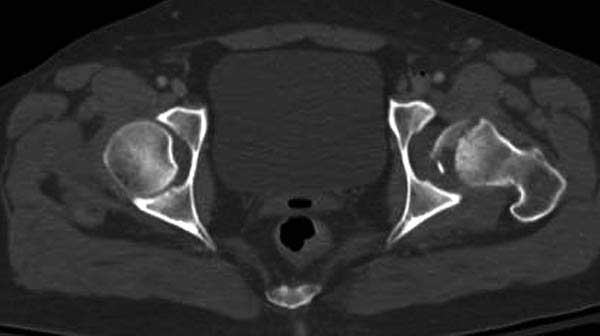

По протоколу обследования больных с травмой сделаны все исследования и выставлен диагноз: разрыв печени и селезенки; множественные переломы ребер и лицевого черепа; стабильный перелом позвоночника, переломо-вывих головки левого бедра, перелом диафиза правого бедра, переломо-вывих правого тарана.